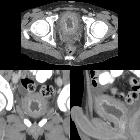

Teenager with

new hematuria who is being treated with cyclophosphamide for lymphoma. Axial (above), coronal (below left) and sagittal (below right) CT with contrast of the abdomen shows diffuse thickening of the bladder wall and hyperemia of the bladder mucosa. The diagnosis was cyclophosphamide induced cystitis.